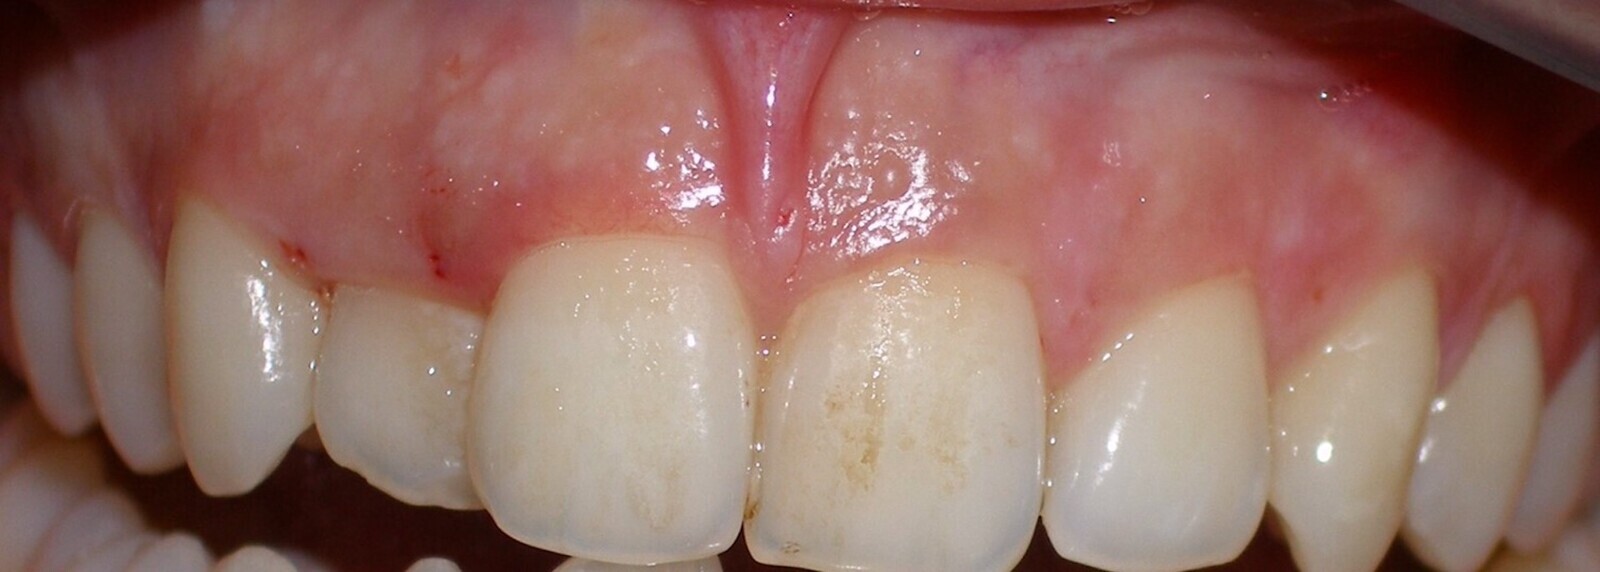

El tratamiento de estas pigmentaciones con el láser de diodo obtiene buenos resultados a nivel estético, es cómodo para el paciente durante y después de la intervención, y los resultados son muy estables a lo largo del tiempo (Figuras 6-8).

El láser de diodo obtiene buenos resultados estéticos en el tratamiento de pigmentaciones (ver Figuras 6-8).

Figura 6.

Figura 7.

Figura 8. Las figuras 6-8 muestran el tratamiento de las pigmentaciones con el láser de diodo obtiene buenos resultados a nivel estético y es cómodo para el paciente.